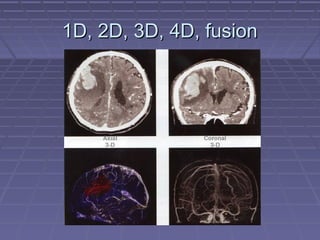

 1D, 2D, 3D, 4D1D, 2D, 3D, 4D

 Different DICOM Modality type: Cardiac / PET / 4DDifferent DICOM Modality type: Cardiac / PET / 4D

1D, 2D, 3D, 4D, fusion1D, 2D, 3D, 4D, fusion